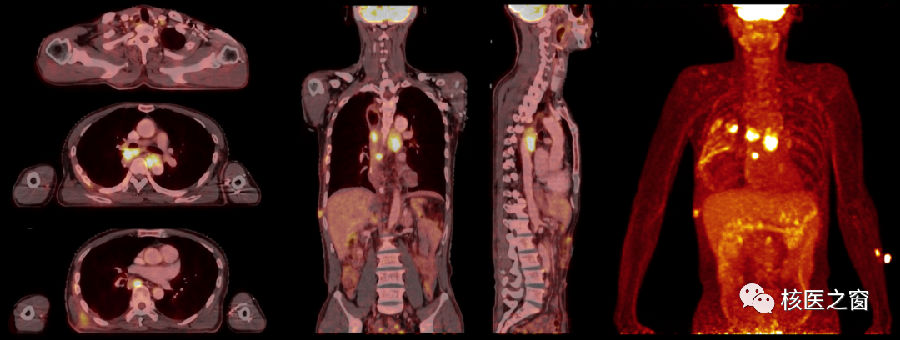

除了上皮来源的恶性肿瘤,血液系统疾病也可以通过PET/CT检查更好的进行临床分期、疗效评估。治疗前、中及治疗后三次PET/CT检查也可以很好的展示治疗效果,下图为一名淋巴瘤患者的精准诊疗过程。

治疗前PET/CT显示淋巴瘤病灶(左图);治疗中期(中图)淋巴瘤病灶缩小、活性降低;治疗结束后再次评估(右图)淋巴瘤病灶活性被完全抑制。